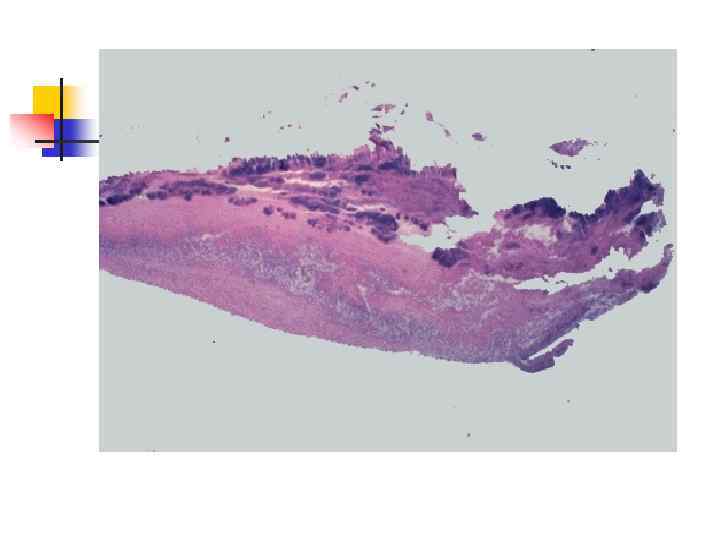

n n Септический или бактериальный эндокардит (sepsis lenta) обычно вызывается белым и золотистым стафилококком, зеленящим стрептококком (преимущественно L- формы и мутанты), реже гемолитическим стрептококком, пневмококком, энтерококком, кишечной и синегнойной палочками. Септический эндокардит является результатом гиперергии, по сути септицемией с септическим очагом на клапанах сердца (чаще аортальных). В основе гиперергии лежат реакции гиперчувствительности, обусловленные воздействием циркулирующих в крови токсических иммунных комплексов, которые содержат антиген возбудителя. С циркуляцией в крови иммунных комплексов связаны такие проявления септического эндокардита как генерализованные васкулиты, резкое повышение сосудистой проницаемости, тромбоэмболический синдром, клеточные реакции стромы и др.

n n Бактериальный эндокардит разделяют по характеру течения (острый около 2 недель, подострый - до 3 мес. , затяжной - многие месяцы и годы) и наличию или отсутствию фонового заболевания (развивающийся на порочных клапанах - вторичный, составляет до 80% случаев; и первичный - на интактных клапанах). Сердце увеличивается в размерах за счет левого или правого отделов в зависимости от характера порока (аортального или митрального), пораженные клапаны склерозированы, резко деформированы и покрыты значительными тромботическими наслоениями.